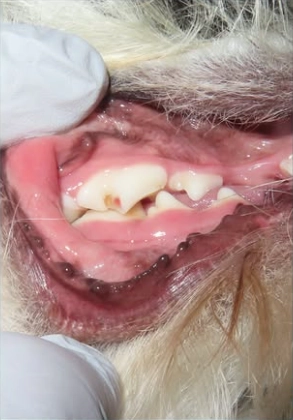

강아지 치아 파절 신경 치료 사례

치아 파절로 신경이 노출된 강아지를 진단한 뒤 손상된 치아를 처치해 통증과 염증을 완화했습니다.

소형견 치주염 발치 및 치주 치료 사례

소형견에서 진행된 치주염을 방사선 검사로 정확히 진단한 뒤 상태에 따라 발치와 치주 처치를 진행했습니다.

노령견 중증 치주염 발치 치료 사례

심한 치주염이 진행된 노령견을 진단한 뒤 통증의 원인이 된 치아를 발치하고 치주 처치를 진행했습니다.